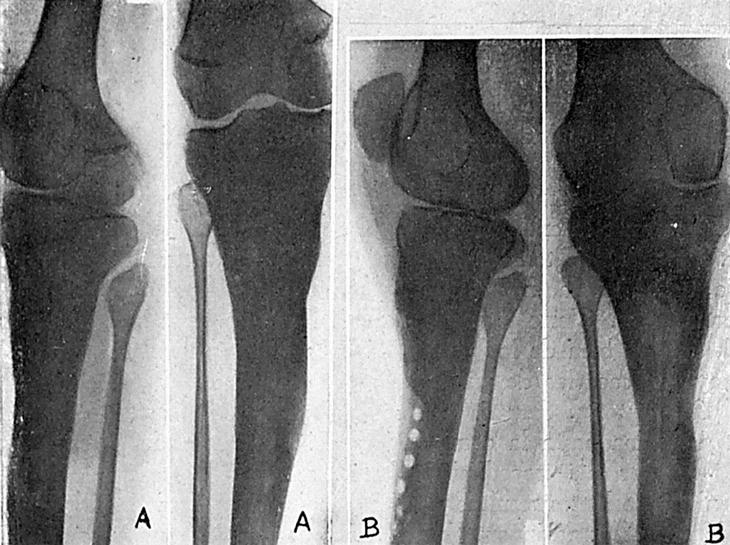

El día 20-X-46, dolor muy intenso en tercio superior de tibia derecha; elevaciones térmicas hasta 38,6°. Leucocitosis, 12.300, con 80% de polinucleares. Radiográficamente, zona de condensación ósea en tercio superior de tibia con cavidad en el centro de la misma (fig. 1A).

Figura 1.

Previo tratamiento con penicilina, es intervenido el 14-XI-46. Extirpación de una zona amplia de hueso que comprende la cavidad del absceso óseo hasta llegar a hueso sano. Se rellena la cavidad con un colgajo del gemelo interno. Cierre de la herida, dejando dos drenajes de vidrio, que son retirados el 17-XI. Cicatrización por primera intención. Alta el 25-XI-46.

Revisado el enfermo el 19-II-47 (fig. 1B).

El 2-IV-47, aumento de volumen muy acentuado de extremidad superior de pierna izquierda, piel edematosa, absceso en cara medial de pierna, tres trayectos en cara anterior de tercio superior de pierna que dan salida a un pus abundante. Al análisis directo, estreptococos. Radiográficamente, extensas lesiones en los dos tercios superiores de tibia (fig. 2A).

El 20-IV-47, previo tratamiento con penicilina, incisión que, comenzando en tuberosidad anterior de tibia, se extiende hasta el tercio inferior. Extirpación de la piel entre los trayectos fistulosos, así como la que lo rodea. Amplia exéresis de las lesiones óseas, quedando una gran cavidad cuyas paredes están constituidas por una cortical muy adelgazada y con una extensión aproximada de los dos tercios de su circunferencia y que se extiende desde las proximidades del cartílago epifisario hasta la parte media de la tibia. En algunos puntos de esta superficie falta la cortical, quedando orificios que comunican con el absceso de las partes blandas. Extirpación de las paredes del absceso. Taponamiento, con gasa, de la cavidad, y cierre de la herida operatoria, dejando dos drenajes de vidrio y continuando el tratamiento de penicilina.

El 3-V-47 se abre la herida operatoria, siendo necesario extirpar los bordes de la misma que están macerados, se retira la gasa y se rellena la cavidad con tejido esponjoso. La cavidad es tan grande que, para rellenarla, es necesario sacar todo el tejido esponjoso de ambas crestas ilíacas y de la metáfisis superior de la otra tibia. Para cerrar la herida de piel, sin tensión, es necesario practicar una incisión liberadora en cara medial de pierna, quedando en este sitio una superficie cruenta sin cubrir. Vendaje compresivo y penicilina, local e intramuscularmente.

El 18-V-47 se quitan los puntos, habiendo cicatrizado por primera intención (fig. 2B). La radiografía en esta fecha permite apreciar la amplia extirpación ósea, así como la tendencia a organizarse de los injertos rellenos (fig. 2C).